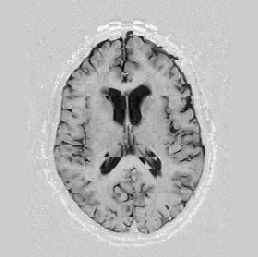

The results are shown for another pair of images in Figure [*].

Figure: Multi-scale NRR. From left to right, top then bottom: before NRR; after 5 iterations of NRR at level 2; after another 5 iterations of NRR at level 1.